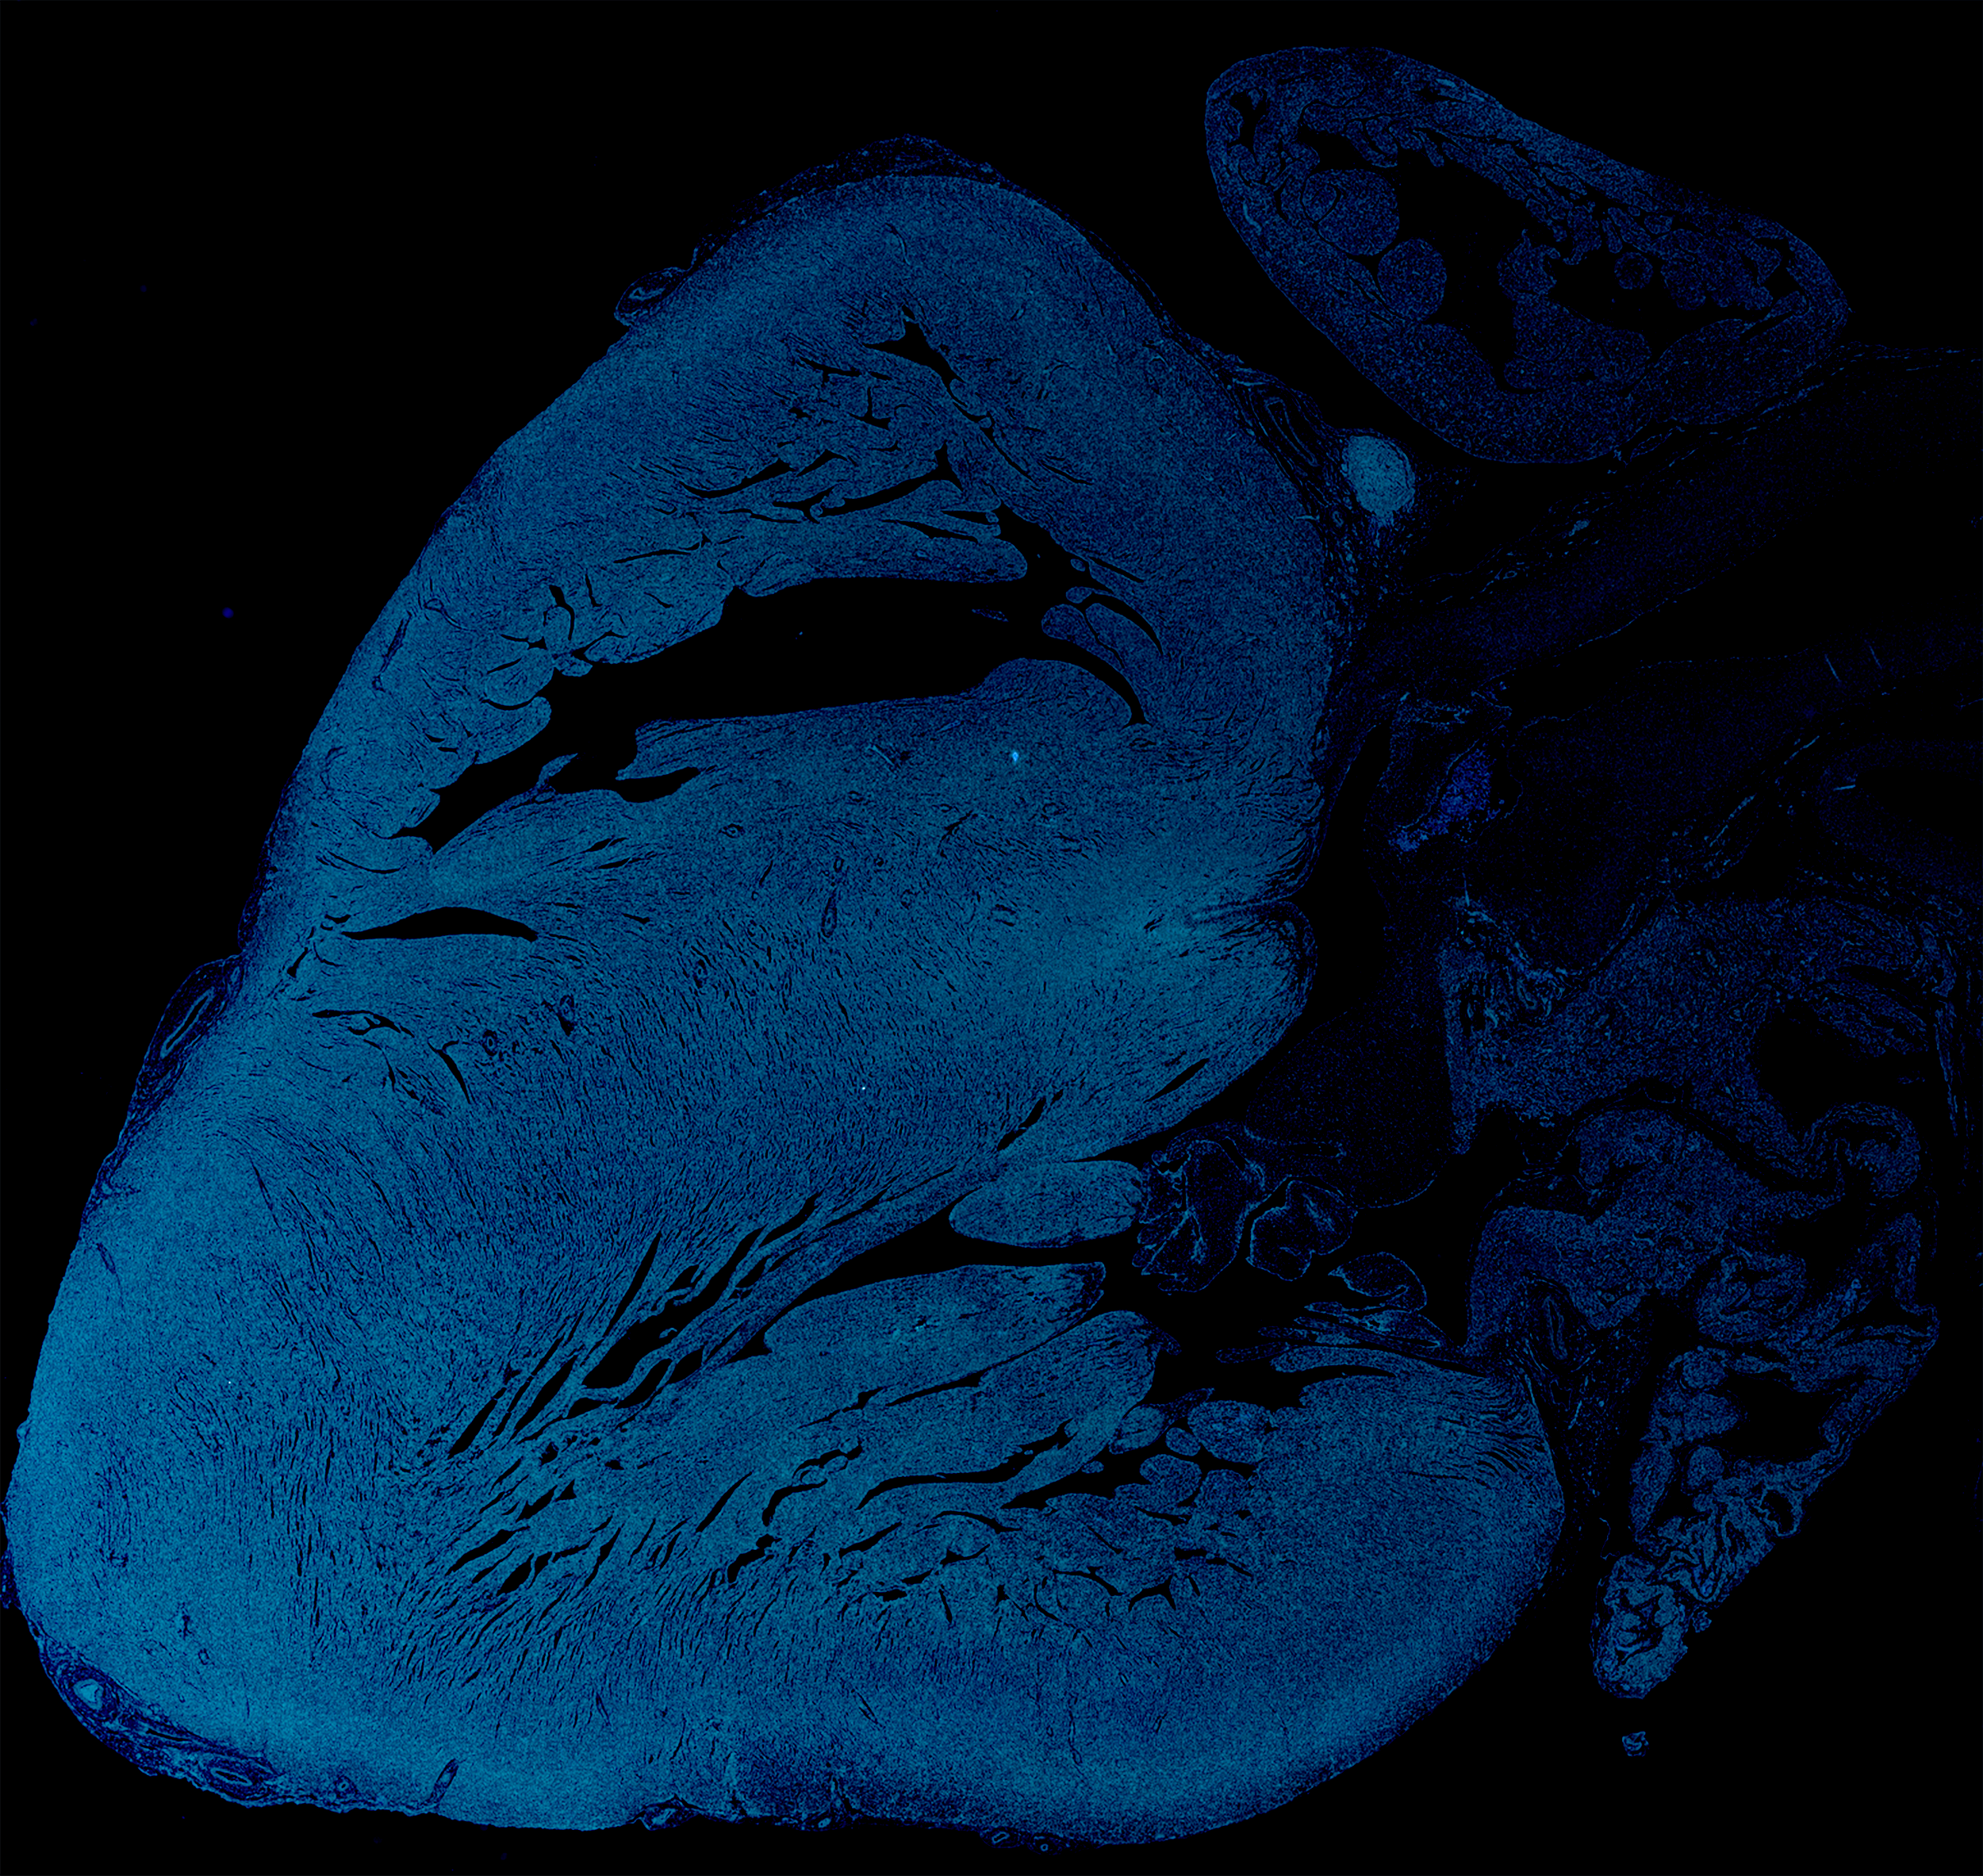

How we piece the heart together

Our expert researchers use many complementary techniques and methods to solve the mysteries of cardiac development. From animal models and experiments to machine learning and big data, the CellTalk-HHD consortium coordinates its approach across the institutes involved to triangulate on the communication taking place within the growing tissue.

Mice

/